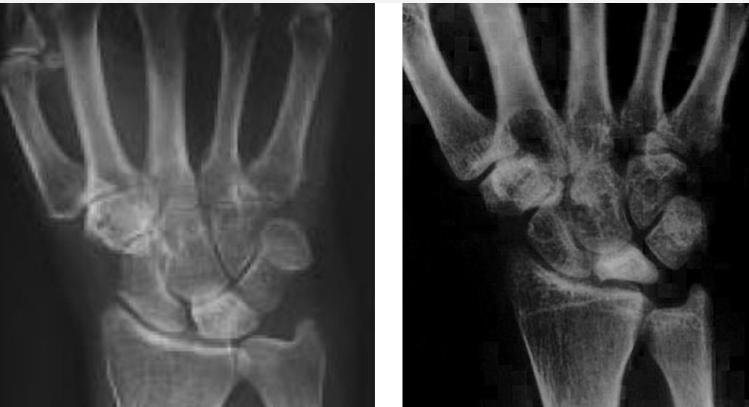

Qual as etiologias prováveis para inicio da doença de kienbock ?

A

Trauma prévio

Microtraumas repetitivos

Ulna minus (foto)

Insuficiência arterial

Formato do semilunar triangular

Descreva o estadiamento de Lichtman

I: Rx normal, podendo apresentar fratura

II: Aumento da densidade do semilunar sem colapso

IIIA: fragmentação do semilunar com colapso, porém sem instabilidade

IIIB: Fragmentação do semilunar com colapso e desalinhamento (instabilidade) carpal

IIIC: Fratura coronal cronica do semilunar

IV: alterações artrósicas perilunares